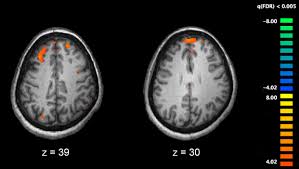

An Integrative And Mechanistic Model Of Impaired Belief Updating In Schizophrenia Journal Of Neuroscience

An Integrative And Mechanistic Model Of Impaired Belief Updating In Schizophrenia Journal Of Neuroscience from www.jneurosci.org